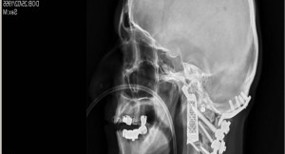

x射线的观点

x射线视图。照片:ABC.net.au